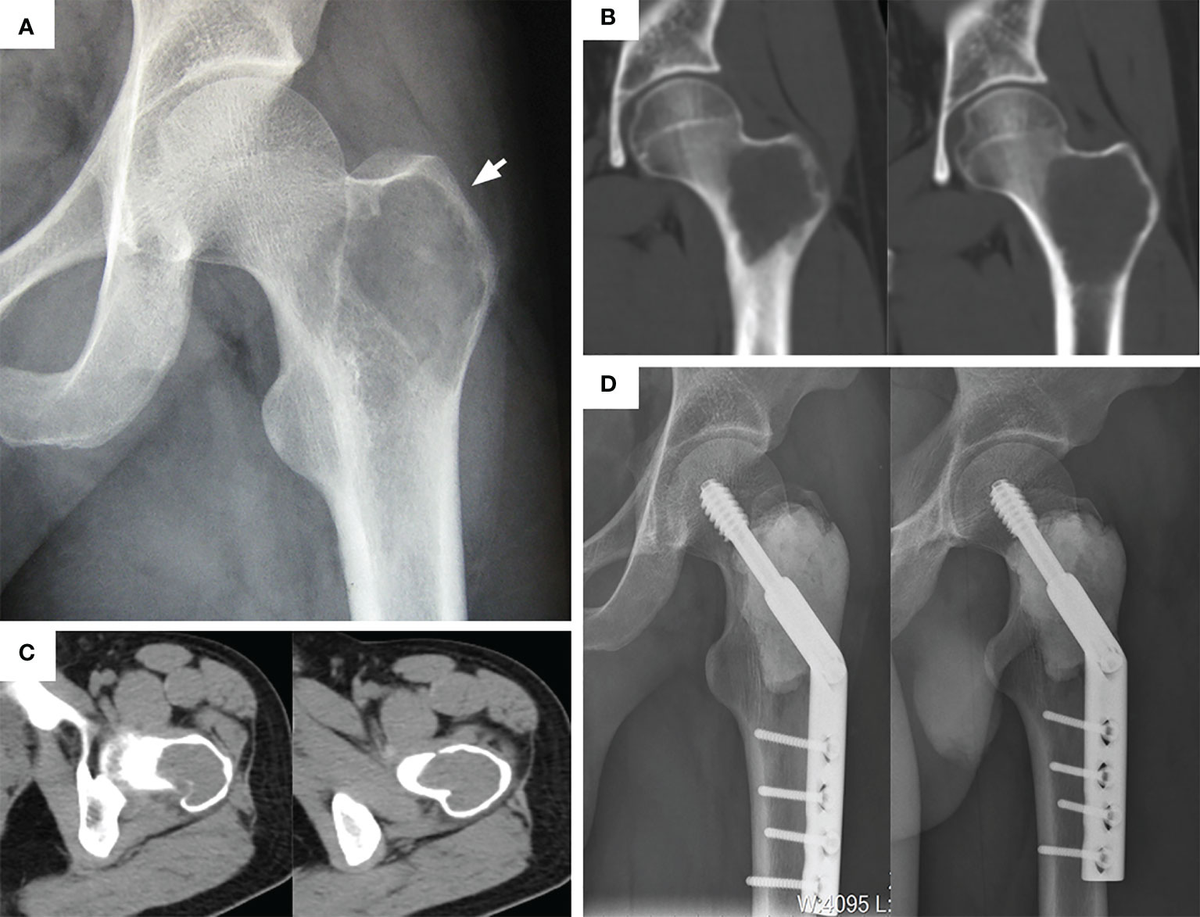

In Plain Sight: An Inconspicuous Case of a Giant Cell Tumor - The American Journal of Medicine

image size: 3167x2274